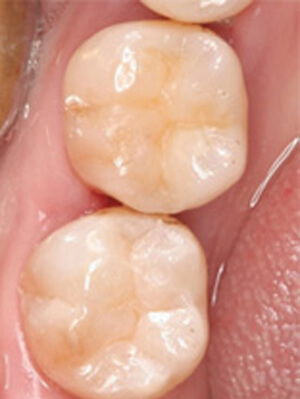

ダイレクトボンディング症例4

虫歯が進行した部分のみを除去

術前

患者さんはダイレクトボンディング法を希望されたため虫歯が進行した部分のみを除去しました(削る量は最小限で済むため歯にやさしい治療です)

ダイレクトボンディング 治療後

術後

ダイレクトボンディング治療後